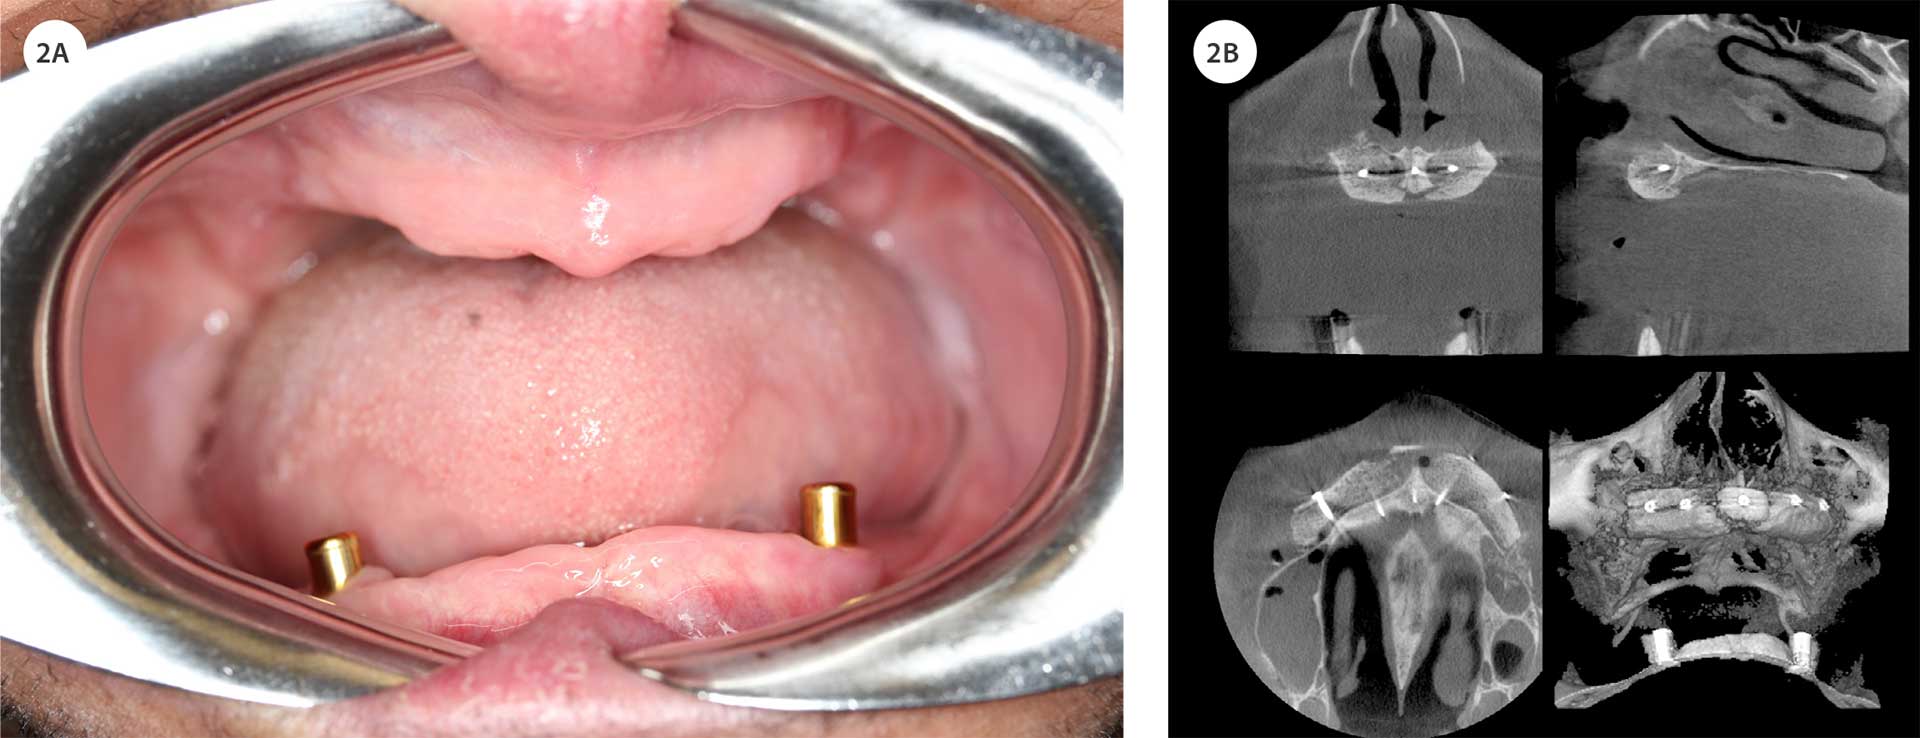

Figur 2. Betydelig kjevekamsatrofi i både over- og underkjeve, men tilstrekkelig til installasjon av 2 implantatet i underkjeven (A). I overkjeven ble det utført rekonstruksjon ved hjelp av autogen benblokk transplantasjon fra hoftekammen. CBCT-bildene viser transplantatet fiksert med titanskruer (B).

Pasienten opplevde total tannløshet i over- og underkjeve som betydelig belastende, både funksjonelt og estetisk. Han uttrykte et klart ønske om en fast protetisk løsning, og ønsket ikke behandling med avtakbar protese. På grunn av alvorlig periodontitt og tidlig tanntap forelå det uttalt kjeveatrofi i begge kjever, noe som kompliserte behandlingsplanleggingen. Ved klinisk og radiologisk vurdering ble det imidlertid konkludert med at benvolumet i underkjeven var tilstrekkelig for innsetting av to implantater som støtte for en dekkprotese (figur 1B, 2A). Overkjeven viste derimot omfattende atrofi, og det ble vurdert som nødvendig med bentransplantasjon fra hoftekam før implantatbehandling kunne gjennomføres (figur 1A, 2A). Pasienten ble grundig informert om behandlingsalternativer, prosedyre og forventet forløp, og ga sitt informerte samtykke til videre behandling.

Pasienten gjennomgikk en ukomplisert implantatinnsetting i underkjeven under lokalbedøvelse. På grunn av usikkerhet rundt mulig penicillinallergi og økt infeksjonsrisiko ved PLS, ble valg av antibiotikaprofylakse tilpasset. Det ble gitt Dalacin pre- og postoperativt. Det ble plassert Nobel Active-implantater (3,5 x 11,5 mm) i områdene 33 og 43 (figur 2A, 3D). Omtrent tre uker etter operasjonen oppsto symptomer på lokal infeksjon med smerte og hevelse i venstre munngulv. Det forelå ingen feber, allmennpåvirking eller svelgevansker. Infeksjonen ble behandlet med ny Dalacin-kur, med tilfredsstillende klinisk respons.